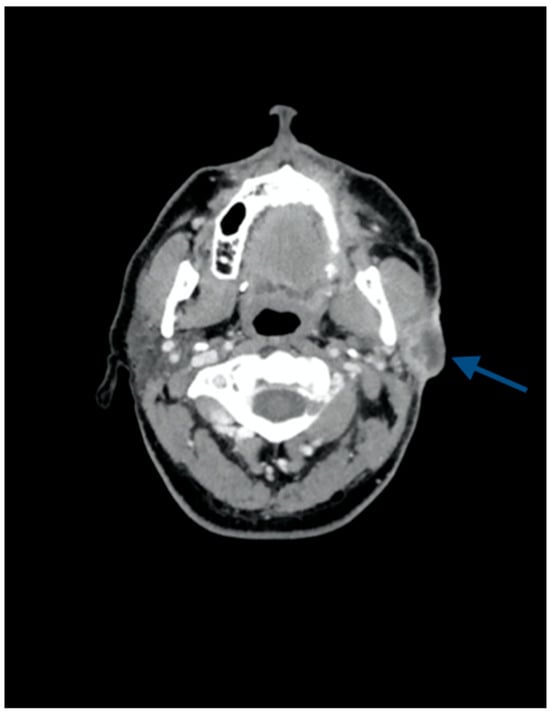

2. Case Presentation